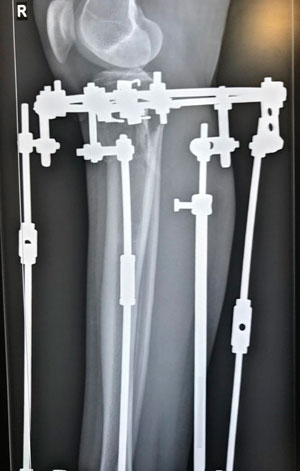

Рентген в 60 дней после операции

Вложения

image-13-03-20-04-23-2.jpg

image-13-03-20-04-23-1.jpg

image-13-03-20-04-23.jpg